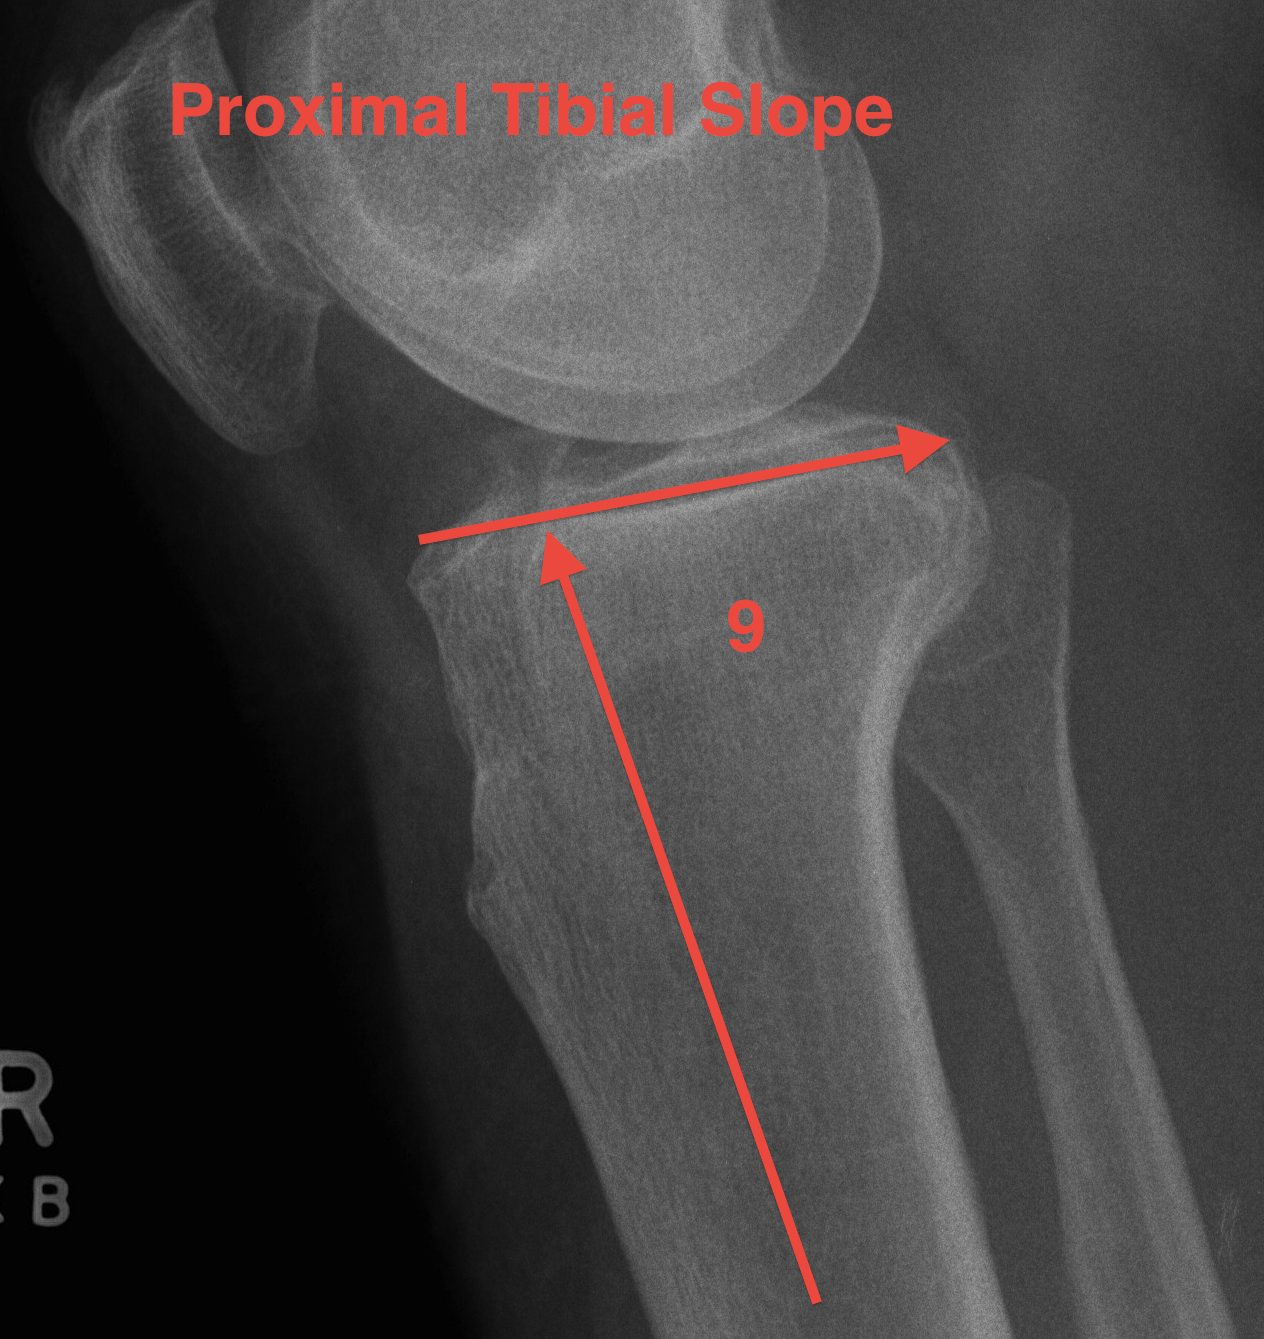

2. Sagittal Plane

Posterior slope

- proximal tibia 10° posterior slope in sagittal plane

- in the knee this is reduced by the menisci